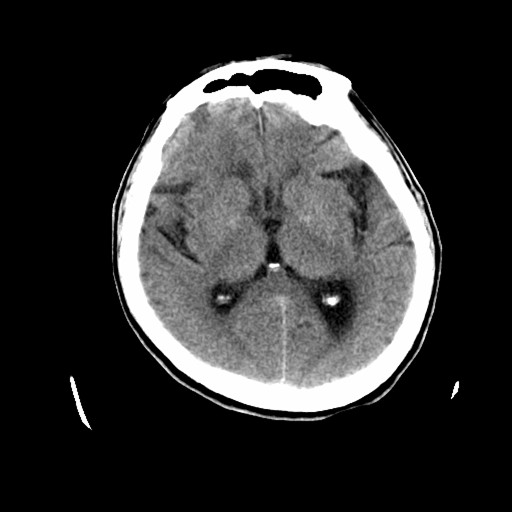

标题: CT19998:男,68岁,突然偏瘫一天 [打印本页]

标题: CT19998:男,68岁,突然偏瘫一天

右侧额叶梗塞

1天梗塞密度也太低点了吧,不除外占位性病变,建议增强.

考虑占位,1级胶质瘤?

分水岭区梗塞

多考虑占位,右侧脑室前角受压。

考虑右侧额顶叶脑梗塞。

支持梗塞表现

好像只能以梗死来解释。